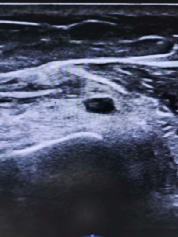

病例二:一位四十九岁的女性患者在外院进行左上臂脂肪瘤切除术后,不幸出现了左侧腕关节无力伴下垂的症状。在泰康医院,疼痛科赵达强主任通过超声细致扫查,发现患者桡神经内存在疑似线头的异常声影。这一线索引起了赵主任的高度重视,随后神经外科医生进行了桡神经探查术,证实了桡神经确实受到手术缝线的损伤,并成功移除了残留的线头。术后,赵主任采用超声引导技术对桡神经进行了修复治疗,超声图像清晰地显示出桡神经被术后瘢痕紧密包裹,导致了神经肿胀,功能难以恢复。借助“火眼金睛”——超声技术的精准辨识,赵主任小心翼翼地将神经与瘢痕分离,并观察到修复药物在神经周围均匀扩散。经过一个多月的持续治疗,患者的左腕关节功能正在逐渐恢复。

(超声图附加说明:穿刺针分离桡神经周围的瘢痕包裹)

(手术后)